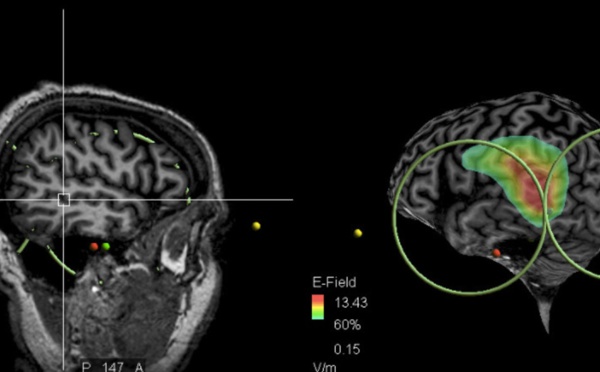

Identifican la zona del cerebro implicada en las voces que oyen los esquizofrénicos - 07/09/2017

Científicos franceses han identificado por vez primera la zona del cerebro implicada en las voces que oyen las personas con esquizofrenia. Es una zona cerebral específica del lóbulo temporal asociada a la lengua. También han descubierto que se pueden mitigar los síntomas con estimulación magnética transcraneal aplicada a esa zona. Una esperanza para pacientes y familiares.